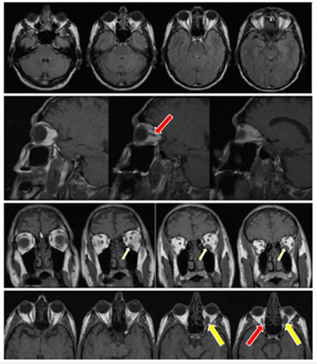

Figure 2: Magnetic resonance imaging (MRI) - Line 1: axial section in the Flair sequence

Line 2: sagittal section, in T1 sequence. Line 3: coronal section, in T1 sequence. Line 4: axial section, in T1 sequence. Showing typical findings of Graves' orbitopathy with marked fusiform thickening in the fascicles of the bellies of the extrinsic muscles of the right and left orbits (red arrow), severely in the belly of the inferior rectus muscle on the left (yellow arrow).

The first example is of the patient in Report 1, whose asymmetric symptoms suggested an inflammatory pseudotumor on magnetic resonance imaging. This was initially a on specific finding, but when we gathered the clinical, laboratory and imaging data, we validated the diagnosis of Graves' ophthalmopathy. This shows that this diagnostic possibility should be considered, so that there is no delay in detection and initiation of treatment.

In the evaluation, the use of imaging, particularly magnetic resonance imaging (MRI) of the orbits, aims to identify patients with active disease, in order to better select those who would respond adequately to immunosuppressive therapy [4]. MRI can also be useful in the evaluation of atypical cases and unilateral proptosis, such as the patient in report 1, when the differential diagnosis with other diseases is crucial (e.g., retroorbital tumor or cyst) as well as in cases of suspected optic nerve compression causing optic neuropathy.